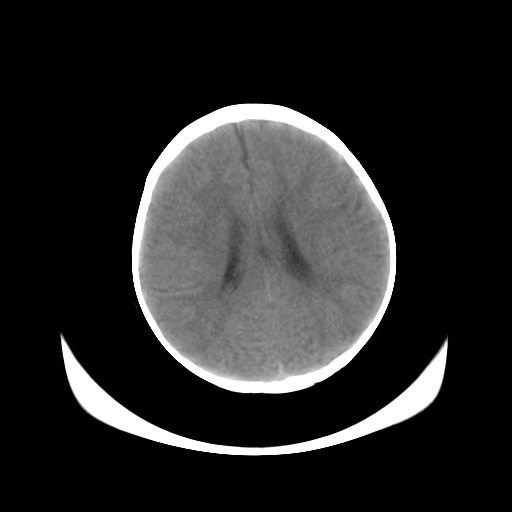

女,10个月,头外伤三天,伤后爱哭闹,吃奶少,睡觉不踏实。

左侧颞极蛛网膜囊肿

1、左侧颞极蛛网膜囊肿;2、第四脑室出血?3、右侧顶叶脑裂畸形伴灰质异位?